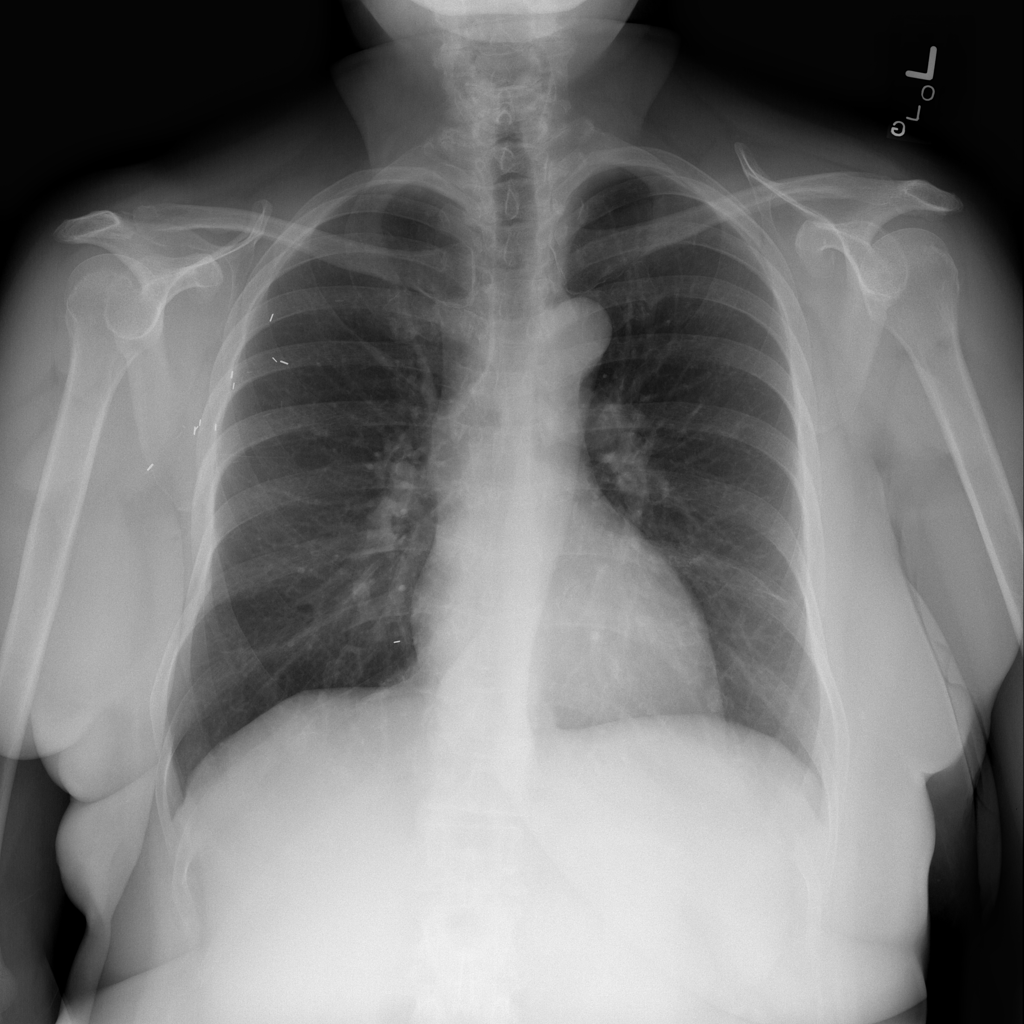

PAT-B625 · IMG-009Atelectasis

PAT-B625 · IMG-009

PA